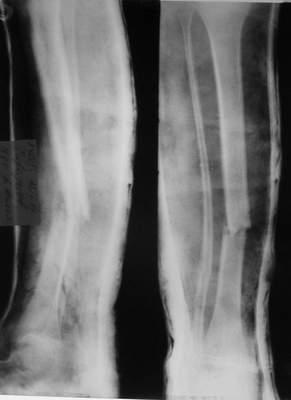

Уважаемые коллеги!Поступила пациентка 40лет, псевдоартроз Н/3 большеберцовой кости, оперирована 1,5-а года назад по поводу перелома ПИЛОНА в Австрии, травма горнолыжная.

после остеосиннтеза |  05.07.04 |  12.04.05 | Пластина удалена через 4-е месяца (миграция винтов), полимерная повязка на 2-а мес. Беспокоит деформация голени,укорочение 1-1,5см, боли незначительные, движения в г/стопном суставе в полном объёме, ходит с полной нагрузкой на ногу, подвижность в переломе не определяется. Одномоментное исправление деформации, костная пластика (chronOS)+ пластина? Аппаратная коррекция, затем пластина? Аппарат? Прошу Ваших советов. С Уважением А.Миронов